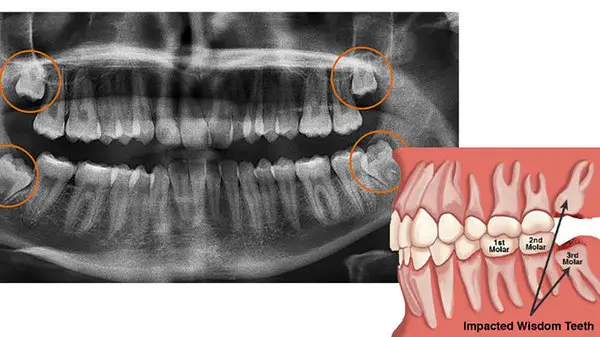

به گزارش رکنا، دندان عقل چون دیرتر از بقیه دندان ها در می آید و در آخرین ردیف قرار دارد اصلا جایی برای رشد ندارد. بنابراین برای خارج شدن از لثه مجبور به هل دادن و فشار آوردن به دندان های بغل است و همین امر سایر دندان ها را کج می کند. همچنین این دندان باعث ایجاد درد در مفصل فک، گوش، چشم و سر هم می شود. بنابراین توصیه می شود که دندان های عقل را قبل از بروز مشکل بکشید مخصوصا اگر فک کوچکی دارید.

کشیدن دندان عقل معمولا طی یک عمل جراحی انجام می شود تا یک یا چند دندان عقل که سومین دندان آسیاب بزرگ دائمی هستند، از دهان بیرون کشیده شوند.

بیشتر ما چهار دندان عقل در انتهای هر قوس دندانی داریم. اما از آنجایی که دندان های عقل آخر از همه بیرون میزنند، در بسیاری از مواقع فضای کافی برای رشد آنها باقی نمانده است در نتیجه نمیتوانند کامل یا صاف و مرتب بیرون بزنند. این ممکن است باعث درد یا عفونت شود. در نتیجه تصمیم بر کشیدن دندان عقل گرفته می شود.

با این وجود، در بسیاری از موارد دندان عقل فضای کافی برای رشد مناسب ندارد و مشکلاتی ایجاد می کند. ممکن است دندان همراستا با بقیه دندانها نباشد و با زاویه و یا حتی به صورت خوابیده قرار گرفته باشد. در این حالت مشکلاتی هنگام بیرون زدن آن به وجود می آید. مشکلاتی که دندان عقل ممکن است ایجاد کند به صورت زیر است:

کاملا نهفته در زیر لثه باقی می ماند. اگر دندان نتواند بیرون بزند، بخشی از آن یا همه آن در فک گیر می کند. گاهی این باعث عفونت یا تشکیل کیست می شود که به بقیه دندانها یا حتی استخوان فک، صدمه می رساند.

دندان عقل نیمه نهفته مانده است یعنی بخشی از آن بیرون زده است اما بخشی از آن هم در زیر لثه مانده است. این وضعیت باعث می شود تمیز کردن دندان سخت تر شود. در نتیجه پلاک و باکتریها راحت تر اطراف آن جمع می شوند و عفونت و پوسیدگی ایجاد می کنند.

دندان عقل فضای کافی ندارد و با فشاری که به بقیه دندانها وارد می کند، باعث کج شدن آنها می شود.